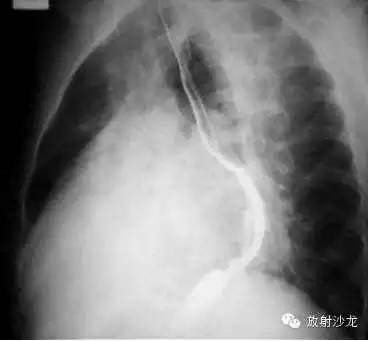

侧位(Left lateral view),心影从后上向前下倾斜。心前缘: 1.升主动脉;2.右室漏斗部与肺动脉主干;3.右室心后缘;4.左心房;5.左心室。

3、侧位:食道前间隙消失,心后间隙变窄。